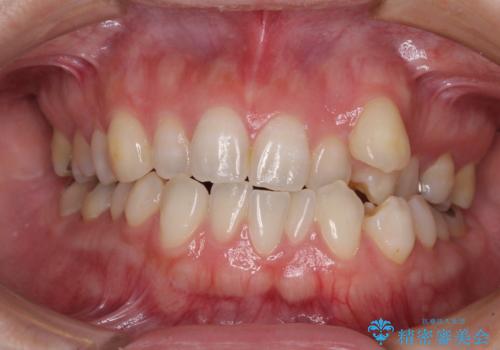

前歯の叢生をいつの間にか改善 インビザラインによる矯正治療